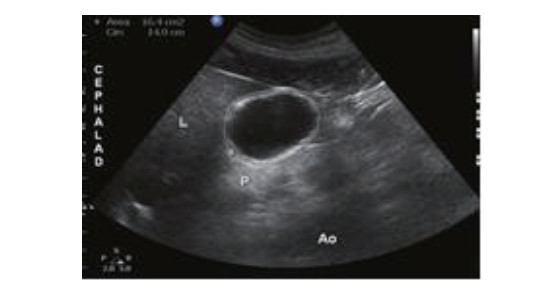

1.2.1 ①胃窦超声评估利用床旁超声机Sonosite M-Tube进行检测,利用2~5 MHz凸阵探头,患者取仰卧位或右侧卧位(因病情危重无法右侧卧位者取仰卧位),床头抬高30~45°,探头方向与身体纵轴平行,在剑突下于正中矢状线右侧获取清晰胃窦部超声[1],见图 1。

| 图 1A 胃窦超声检查部位 |

| 图 1B 胃窦超声切面及示意 |